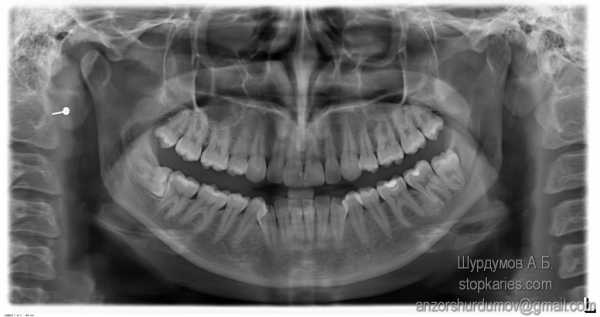

- рентгенограмма: с помощью этого вида диагностики можно «увидеть» скрытые воспаления, переломы корня и другие аналогичные проблемы.

Рентгеновский снимок поможет диагностировать проблему

Сколотые пломбы, трещины в эмали, перелом верхушки корня могут быть вызваны травмами из-за ушибов или пережевывания/надкусывания очень жестких продуктов. Здесь к боли от самой травмы может присоединиться болезненность из-за воспаления (когда инфекция попадает в пульпу через микротрещины). Ощущения могут быть самыми различными – сильными, слабыми, острыми и тупыми. Для правильной диагностики необходимо пройти рентген или ортопантомограмму (ОПТГ).

Хронический фиброзный и гранулематозный переодонтиты на рентгенограмме

На рентгенограмме ретенированные (не прорезывавшиеся) зуб мудрости — 38, 48

У данного пациента множественный кариес, пародонтит, переодонтит нескольких зубов, хронические пульпиты, патология прикуса, повышенная стираемость зубов, клиновидные дефекты. Не правильно расположенные нижние зубы мудрости.